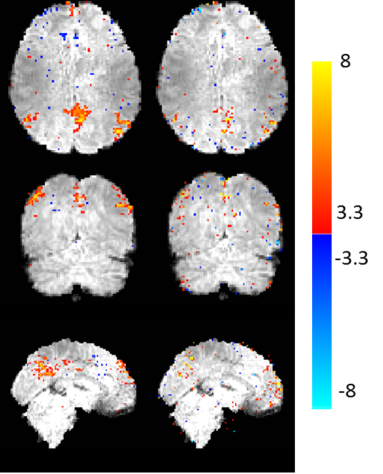

An interesting analysis is the contribution of each component in PEAR. Figure 4 shows the GLM results for the A and P components of PEAR separately (for R=16), where the z-statistics maps are thresholded at and shown with color scale mapped between . Note that the sum of the null-corrected z-statistics maps of A and P is not equal to the z-statistics map of PEAR, due to the null-correction applied for each map, that depends with each map’s noise level. However, the separation of PEAR into periodic and fixed rank components is clearly demonstrated. The A component highly corresponds with the letter “R” which is a purely aperiodic timecourse, and with the letters “M” and “B” that include an aperiodic part. The P component highly corresponds to the letters “F” and “I” which are purely periodic timecourses, and to the letters “M” and “B” that include an periodic part. As demonstrated, this separation allows better modelling and leads to better recovery compared to k-t FASTER and L+S. Another analysis is presented in Fig. 5, where example portions of the mean timecourses from the five letter ROIs are shown for the ground truth, L+S, k-t FASTER and PEAR reconstruction results, including the timecourses for the A and P components of PEAR separately. The timecourses are shown in arbitrary units, to allow proper examination of their structure. It can be seen that as expected, L+S is limited in its ability to track the rapid changes that appear in the letter “R”. In addition, the P component of PEAR indeed contains the periodic part of the signal, and therefore exhibits high correspondence with letters that are fully periodic (“F” and “I”).

PEAR: A component PEAR: P component

Finally, we examined the separation of PEAR into into A and P components, in terms of both time courses and spatial z-stat maps (for R=6.66). For this purpose, we first performed dual regression analysis for the A component and for the P component separately, to generate a z-stat map for each. Those maps, thresholded at and with color scale mapped between , are shown in Fig. 10 and demonstrate that both A and P components contain functional activity. Then, we arbitrary selected a single pixel that exhibited high correspondence with DMN for both A and P (z-stat value of ). Figure 11 shows the timecourses and amplitude spectra of the A and P components, for the selected pixel, where the spatial location of the pixel is shown at the bottom of the Figure. The timecourses and amplitude spectra show that the A component contains a wide range of frequencies, with some strong peaks in the spectrum for frequencies that have strong total energy. The P component contains a limited number of temporal frequencies and captures the low-energy periodicity that is not captured in A. This separation shows that a selection of a fixed, moderate rank for the A component, in addition to a demand for a limited number of temporal frequencies for the P component leads to the desired separation, which results in improved z-stat results shown earlier.